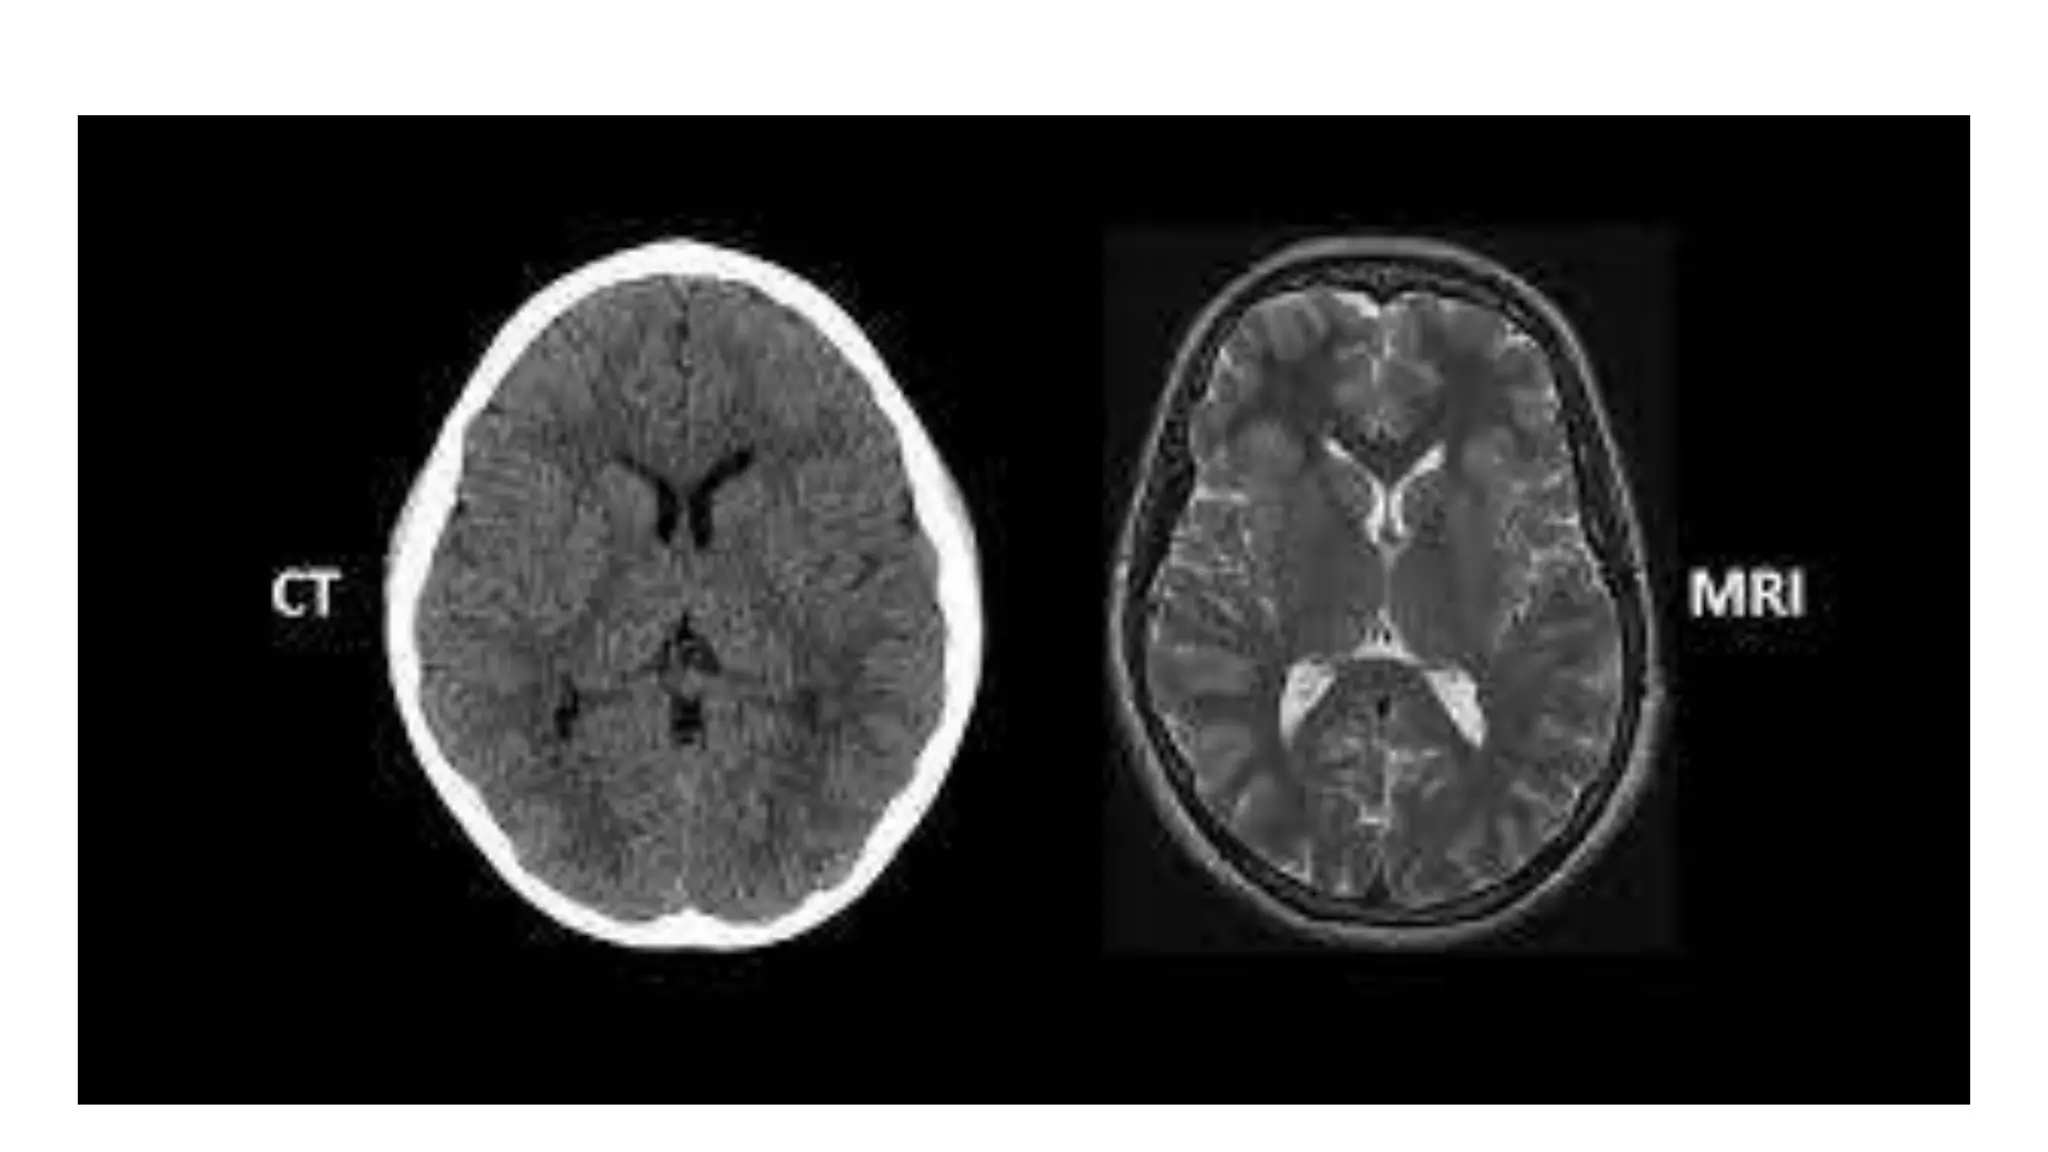

The document is an introductory guide to radiology by Dr. Mathew Joseph, covering the stages of investigations and various imaging techniques, both ionizing and non-ionizing. It outlines the principles of radiology and properties of X-rays, as well as contrast radiography and its applications. The document serves as a foundation for further region-wise radiology classes.